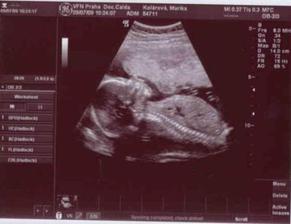

9.7.2009 - Velký UTZ u

Apolináře, vše v pořádku, miminko je

zdravé, děložní hrdlo vypadá v

pořádku, takže prý snad dřív

neporodím a čekáme CHLAPEČKA!!!, který

váží 315 g.

15.7.2009 - 4. poradna, všechno ok,

potvrzený chlapeček 🙂, váha 72 kg